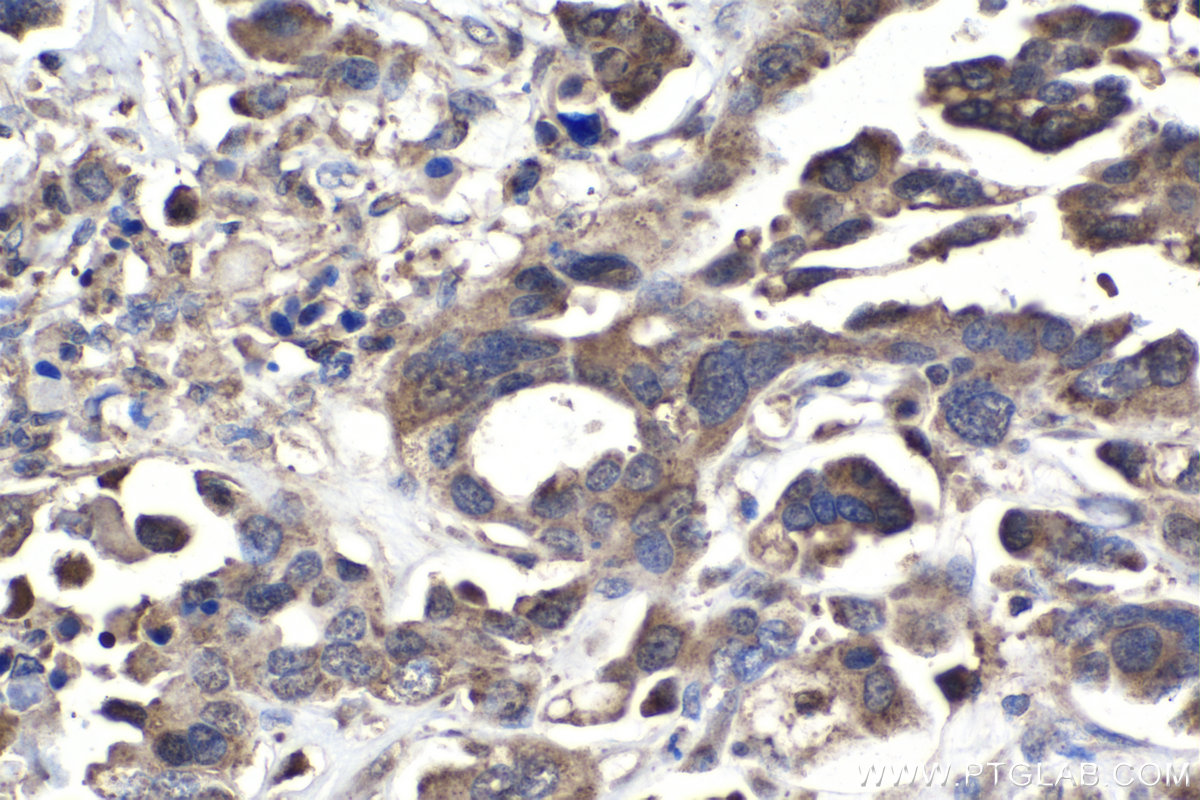

| Positive IHC detected in | human ovary tumor tissue, human colon cancer tissue, mouse liver tissue Note: suggested antigen retrieval with TE buffer pH 9.0; (*) Alternatively, antigen retrieval may be performed with citrate buffer pH 6.0 |

| Immunohistochemistry (IHC) | IHC : 1:500-1:2000 |